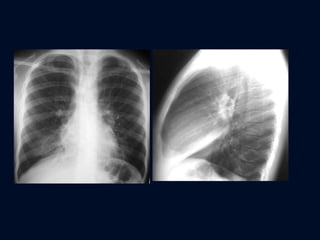

ATELECTASIA LÓBULO SUPERIOR DERECHO Aproximación de cisura menor y mitad superior de la cisura mayor Cisura menor configuración cóncava hacia abajo. Ensanchamiento del mediastino superior en proyección PA Cuña mediastínica en la proyección lateral

ATELECTASIA LÓBULO SUPERIOR DERECHO